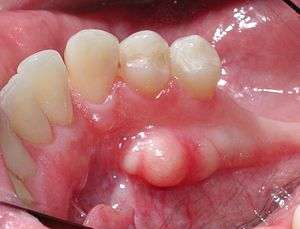

| Mandibular torus in premolar area | |

Torus mandibularis (pl. tori mandibulares) (or mandibular torus (pl. mandibular tori) in English) is a bony growth in the mandible along the surface nearest to the tongue. Mandibular tori are usually present near the premolars and above the location of the mylohyoid muscle's attachment to the mandible.[1] In 90% of cases, there is a torus on both the left and right sides, making this finding an overwhelmingly bilateral condition.